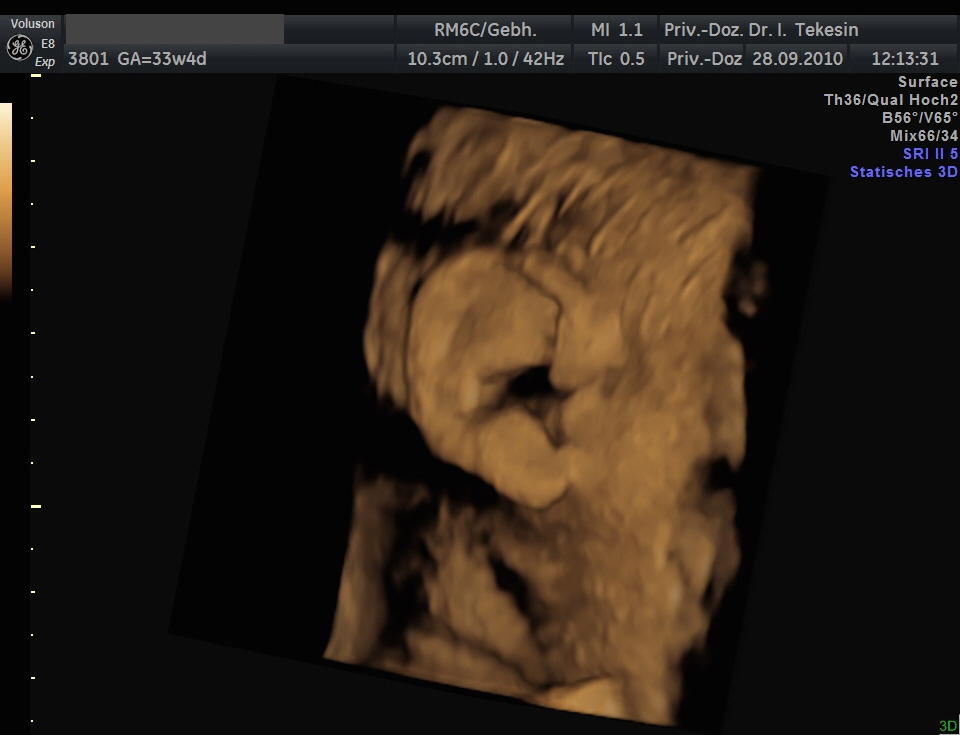

Ohr und Haare in der 34. Woche

Ohr und Haare in der 34. Woche (3D-Darstellung)